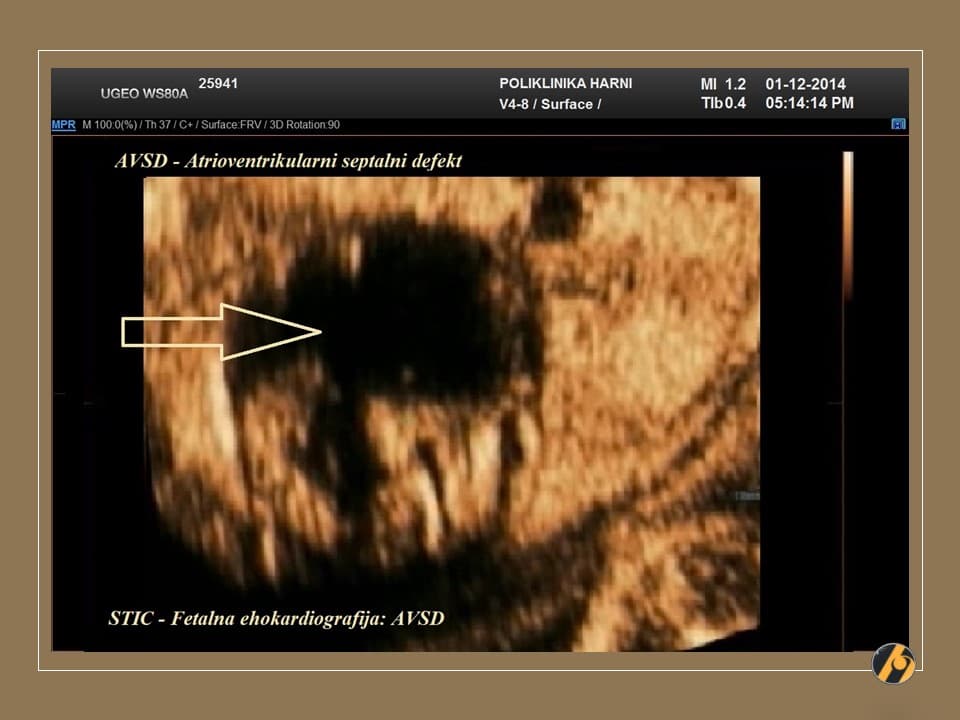

Ovaj pregled omogućuje liječniku da procijeni razvija li se beba uredno te pruža važan uvid u tijek trudnoće, kao i da preporuči dodatne pretrage kao što su fetalna neurosonografija ili fetalna ehokardiografija.